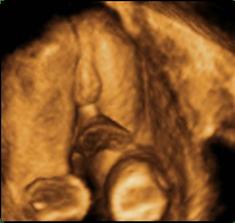

Tešíme sa na nášho drobca